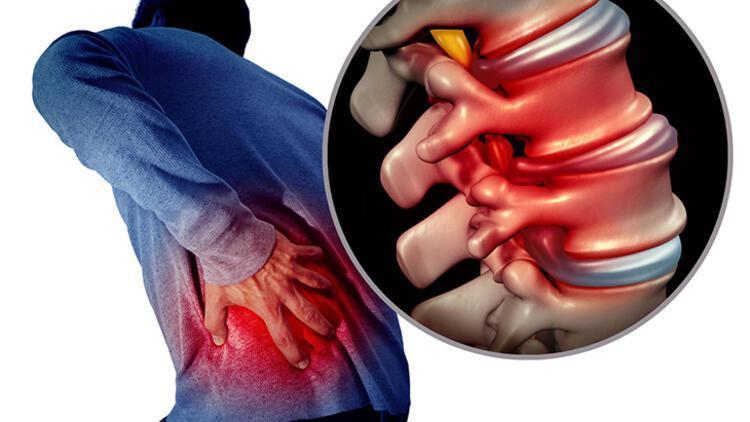

İleri yaşı hasta grubunda omurganın kemik ve kıkırdaklarında yaşlanma ortaya çıkar. Erişkin dönemde görülen skolyozun asıl tetikleyicisi, kıkırdak dokusunun su içeriğini kaybetmesidir. Diskin kireçlenmesi ve yüksekliğini kaybetmesi ile beraber bacaklara giden sinirler sıkışır.

Bacak ve ayaklarda ağrı ve uyuşma şikayetleri ortaya çıkar. Bozulan disk yük dağılımını bozar ve arka tarafta omurganın gücünü artıran faset eklemlere fazladan yük biner. Artan yükler karşı koyabilmek için faset eklem ve omurlar arasındaki bağlar kalınlaşır.

Önden disk dokusunun arkadan sarı ligamentin (Ligamentum flavum) ve faset eklemin büyümesi ile omurilik kanalı iyice daralır. Hastaların yürüyüş mesafeleri iyice kısalır. Omurgadaki bu değişikliklerle beraber omurganın sağlamlığı bozulduğu için omurlar arasında öne, arkaya ve yanlara doğru kayma olabilir.

Bunun sonucu mevcut bel ağrısı şikayetleri daha da artar. Hastanın ön-arka plandaki röntgen filmine bakıldığında omurganın yana doğru eğrildiği görülür. Omurganın eğrildiği taraftaki sinirlerin basıya diğer tarafta ise gerilmeye maruz kalması ile bacaklarda ve ayaklarda, daha fazla ağrı ve uyuşukluk oluşabilir.